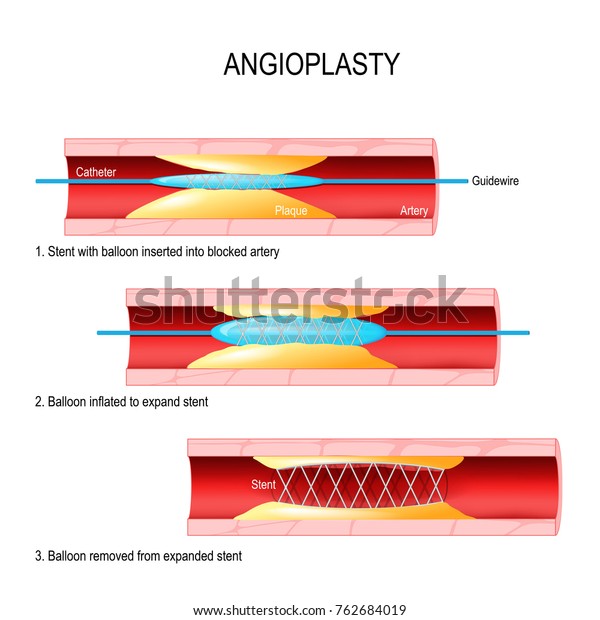

Localized Angioplasty Can Help Men with Heart Disease and ED | Online …

Angioplasty. Stent Implantation. Deflated balloon catheter inserted …